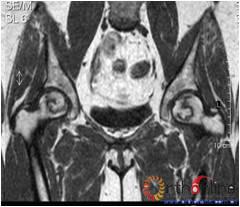

病灶修复情况比较,加用BMP2组病灶修复的完全性及硬化骨数量普遍优于未加BMP2组。(图3)

图3-1 女,31岁,SARS患者骨坏死,(1)MRI示双侧股骨头坏死,右Ⅱb(B型),左Ⅱc(C1型);(2)打压植骨术(未加BMP2)后坏死修复不完全,仍遗留股骨头软骨下病灶未完全修复, 5年随访关节功能优(Harris评分96分)